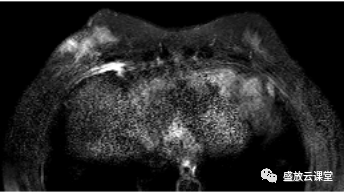

影像学表现

征象分析

特点归纳

诊断结果